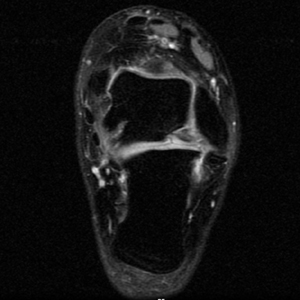

Axial PD fat suppressed FSE

Axial PD fat suppression evaluates the tendons and ligaments of the ankle particularly after acute/subacute injuries. It also is sensitive to talar dome osteochondral defects. Alternatively, a T2 sequence can be used to eliminate magic angle artifact that may occur as the tendons travel around the malleolar turns.